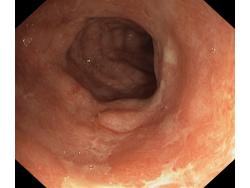

Zapalenie wrzodziejące...

Zapalenie wrzodziejące jelita grubego